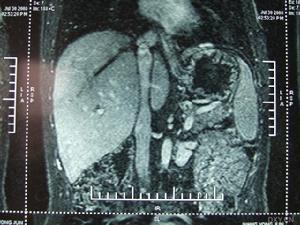

病變累及肝靜脈或以上平面,則可有下腔靜脈高壓、門靜脈高壓(包括肝脾腫大、腹水、食管靜脈曲張和上消化道出血等)和心貯備功能不足(包括動則心悸、氣促)三組臨床表現。急性肝靜脈阻塞可因急劇進行性腹水、肝昏迷而死亡。

如肝腫大、頑固性腹水、上消化道出血、脾大、脾亢、胸腹壁靜脈曲張、下肢水腫及色素沉著等。《布-加綜合症的介入治療》一書由徐州醫學院製作,人民衛生出版社出版,國家衛生部CAI課件,該課件詳細介紹了布-加綜合徵(Budd-Chiarisyndrome)的臨床表現以及影像診斷,通過臨床案例詳細解說,適合醫學院師生以及臨床醫師學習使用。

本CD-ROM為衛生部醫學CAI課件。本課件使用大量珍貴的臨床病例圖片、錄像、動畫和文字,配以解說,詳細介紹了布-加綜合徵(Budd-Chiarisyndrome)的臨床表現以及影像診斷,重點介紹其治療方法,主要包括適應證和禁忌證、介入治療器械、介入治療方法、最新進展、介入術後處理、併發症及處理。課件中附有練習題。課件內容豐富,資料寶貴,是學習布-加綜合徵的不可多得的輔助教材。本CAI課件由徐州醫學院製作,適用於醫學院師生以及臨床醫師學習使用。